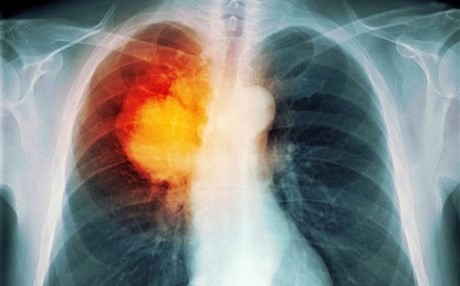

Ένα νέο φάρμακο για μία μορφή καρκίνου του πνεύμονα, που συχνά προσβάλλει νεότερους ανθρώπους και μη καπνιστές, ενέκρινε ο Ευρωπαϊκός Οργανισμός Φαρμάκων (ΕΜΑ).

Το φάρμακο λέγεται σεριτινίμπη (ceritinib) και προορίζεται για τους ασθενείς με προχωρημένο, μη μικροκυτταρικό καρκίνο του πνεύμονα θετικό στην κινάση του αναπλαστικού λεμφώματος (ALK), οι οποίοι έπαψαν να ανταποκρίνονται στις υπάρχουσες θεραπείες ή έχουν δυσανεξία σε αυτές.